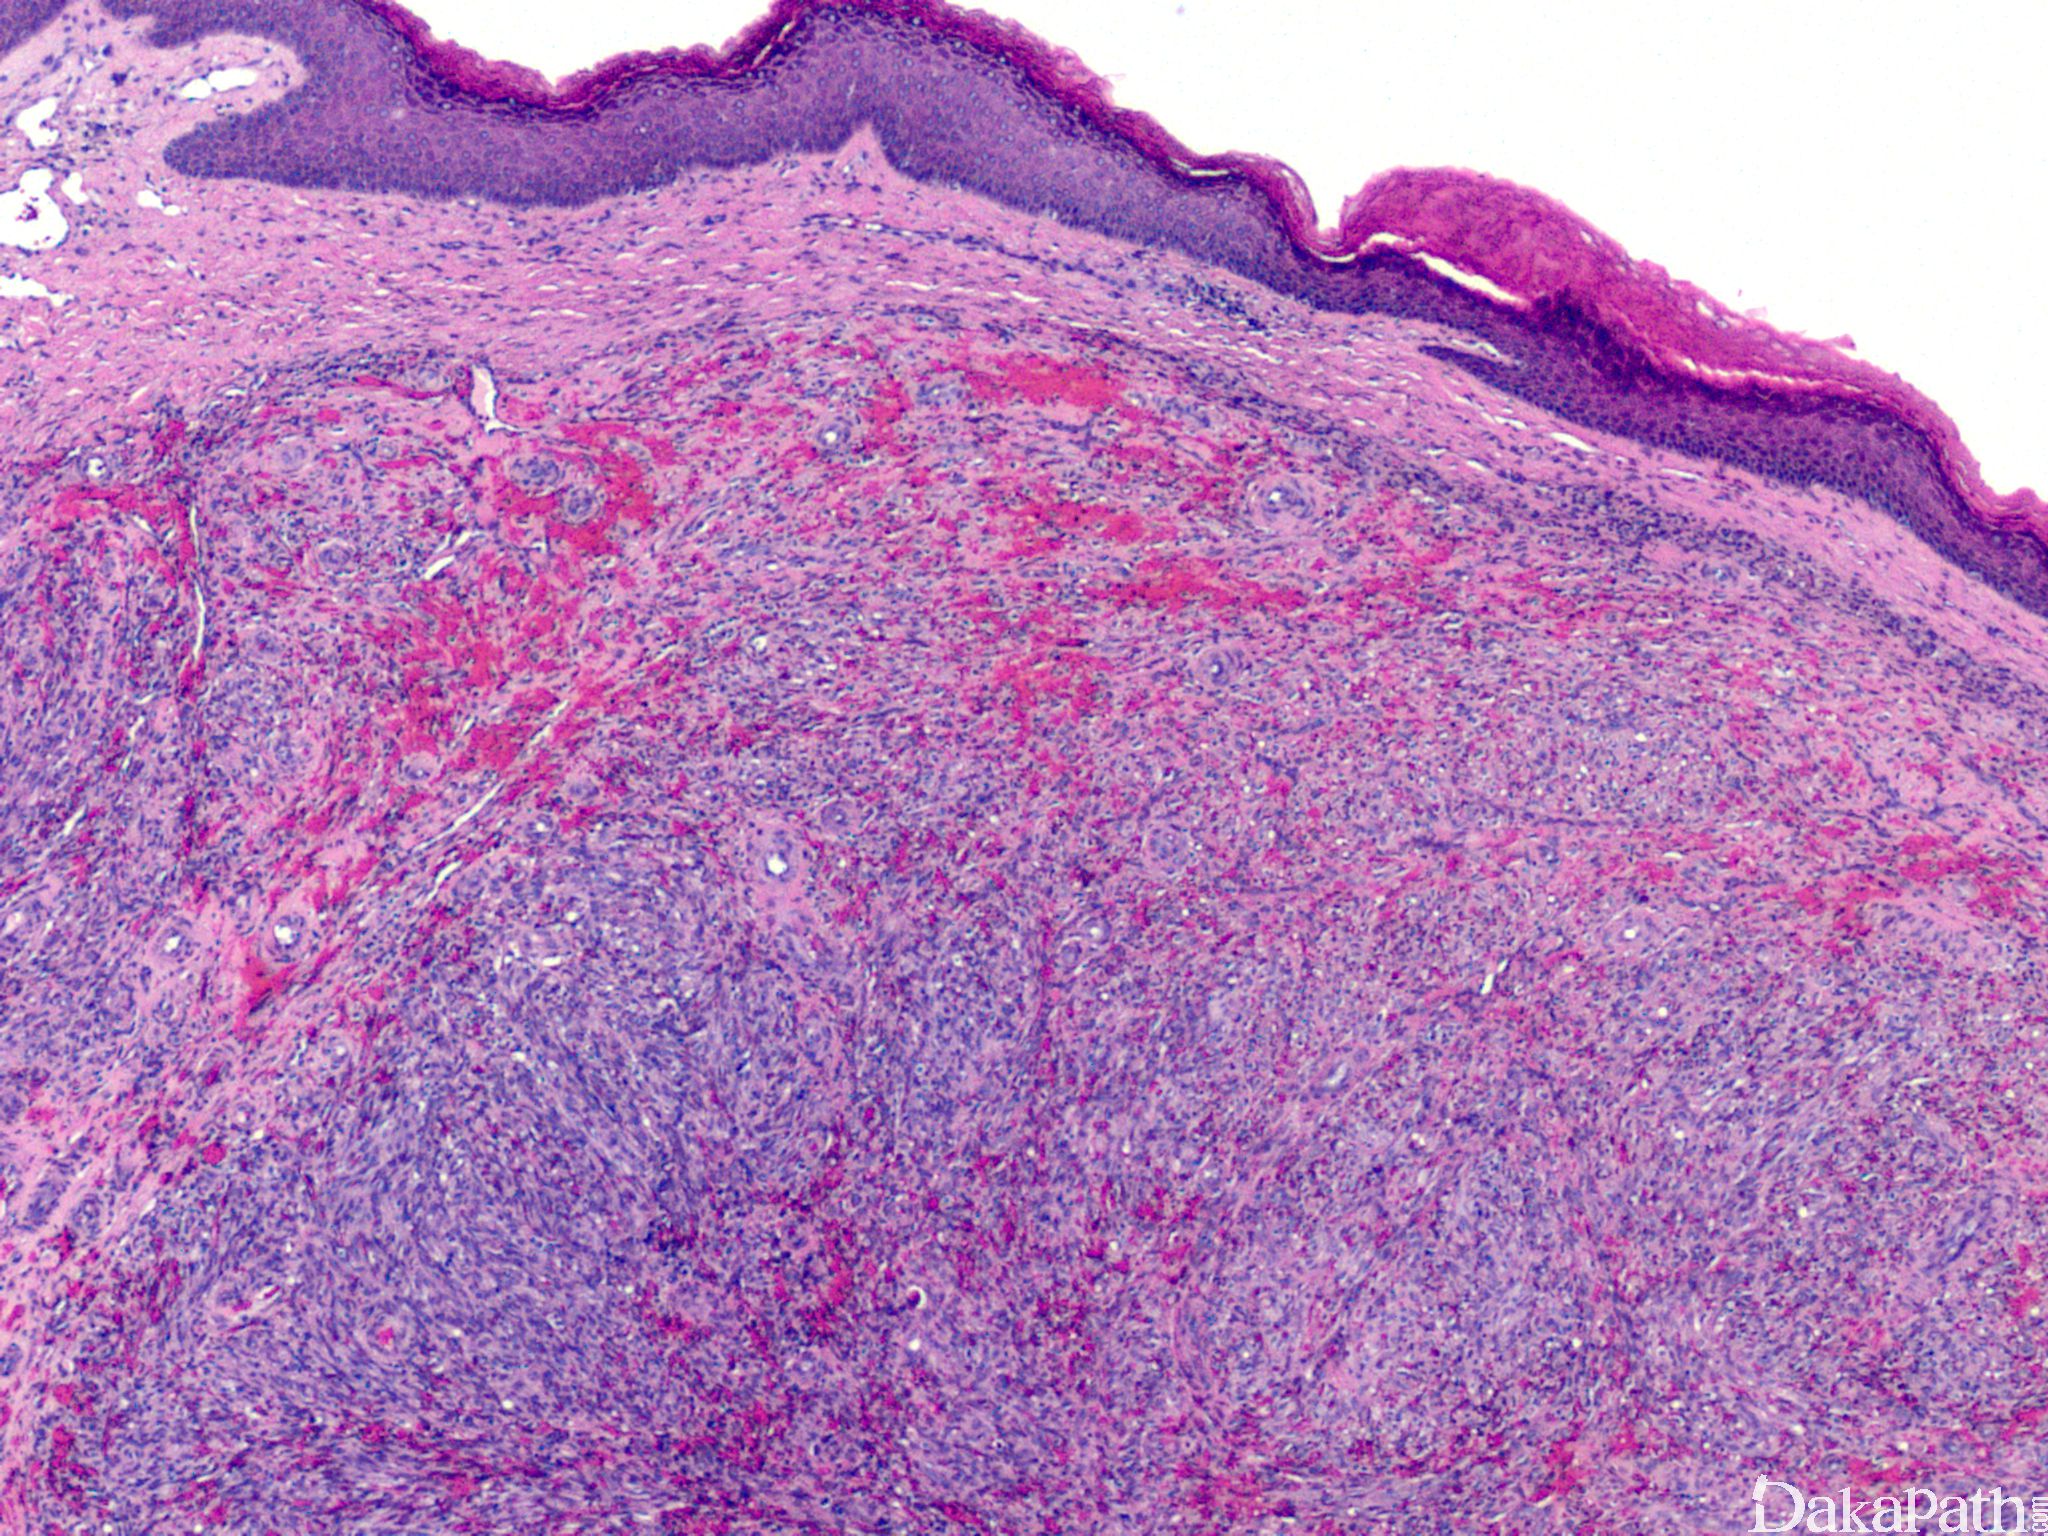

II 期为斑点(斑片)期:变化极似肉芽组织,真皮血管数量增加,形状不规则,在真皮浅层胶原纤维间呈疏松、参差不齐的分支状排列,将真皮胶原纤维分隔。血管周梭形细胞增生、红细胞外渗,间质中淋巴细胞、浆细胞浸润,伴含铁血黄素沉着。

III 期为斑块期:皮肤轻度隆起,病变累及真皮全层或累及皮下组织。与 II 期形态学有明显的重叠,血管增生更广泛,红细胞外渗和含铁血黄素沉着更显著。管腔轮廓呈锯齿状,真皮血管周围嗜酸性梭形细胞增多,炎细胞浸润明显,可见大量的红细胞外渗,含铁血黄素及玻璃样小体。